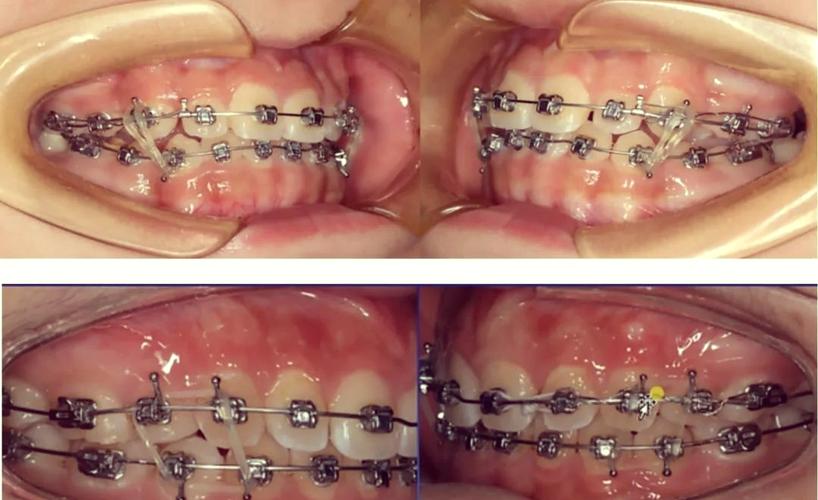

- 调整咬合关系:通过牵引上下颌牙齿,纠正“深覆合”(上牙盖下牙过多)、“深覆盖”(俗称“龅牙”)、“反合”(俗称“地包天”)等异常咬合,II类牵引(上颌向后牵引、下颌向前牵引)可纠正上颌前突,III类牵引则用于改善下颌前突。

- 纠正中线偏移:若上下颌牙齿中线不一致(如上颌中线右偏、下颌中线左偏),可通过交叉牵引(左侧上牙与右侧下牙牵引,或反之)调整牙齿位置,使中线对齐。

- 确认牵引方向:医生会在矫治器上粘贴“牵引钩”(或利用托槽本身的钩子),需明确橡皮筋应挂在“上颌哪颗牙的钩子”与“下颌哪颗牙的钩子”上,避免方向错误(如II类牵引方向反了会导致“龅牙”加重)。

- 挂钩操作:将橡皮筋的一端挂在上颌牵引钩上,另一端轻轻拉伸至下颌牵引钩,确保橡皮筋无扭曲、无松弛(理想状态是橡皮筋被轻微拉伸,但不过度紧绷)。